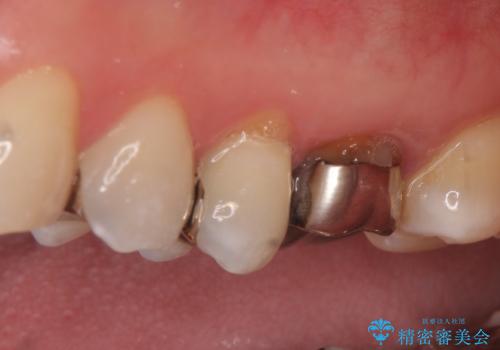

- 左上4、5、6番目の歯を白くしたいといらっしゃった方の症例です。

4番目の歯はセラミックインレーによる修復、5・6番目の歯はオールセラミッククラウンによる補綴を行いました。

左上6番目の歯については再根管治療を行っております。